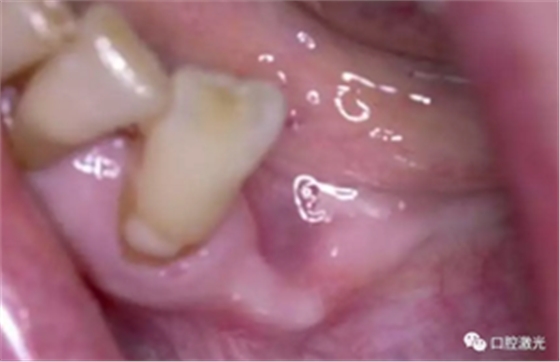

术后4周